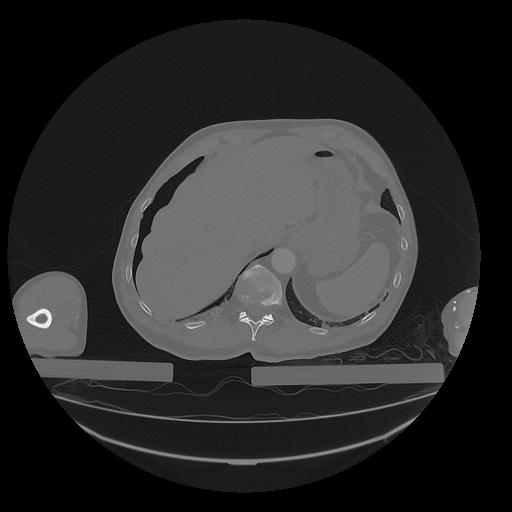

31 PULMON,CE,Vol,1.0,PULMON,,